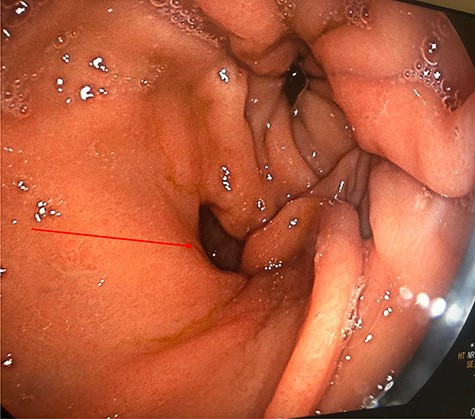

Computed tomography (CT) revealed a complex fistulous communication between the distal stomach and biliary tree with associated pneumobilia, and between the transverse colon and the distal stomach (Fig. 1). No gallstones were seen. Upper and lower gastrointestinal endoscopy was performed, revealing a prepyloric gastric ulceration and fistula (Fig. 2), with no obvious gastric pathology, which extended into the colon and a blind end structure assumed to be the gallbladder. Colonoscopy demonstrated an area of slight narrowing from the hepatic flexure to mid-transverse colon, with macroscopic colitis (Fig. 3). Biopsies were non-specific, with IBD a possibility, but the features were not pathognomonic.

Lower GI endoscopy demonstrating ulceration, stenosis and stricturing of the transverse colon.